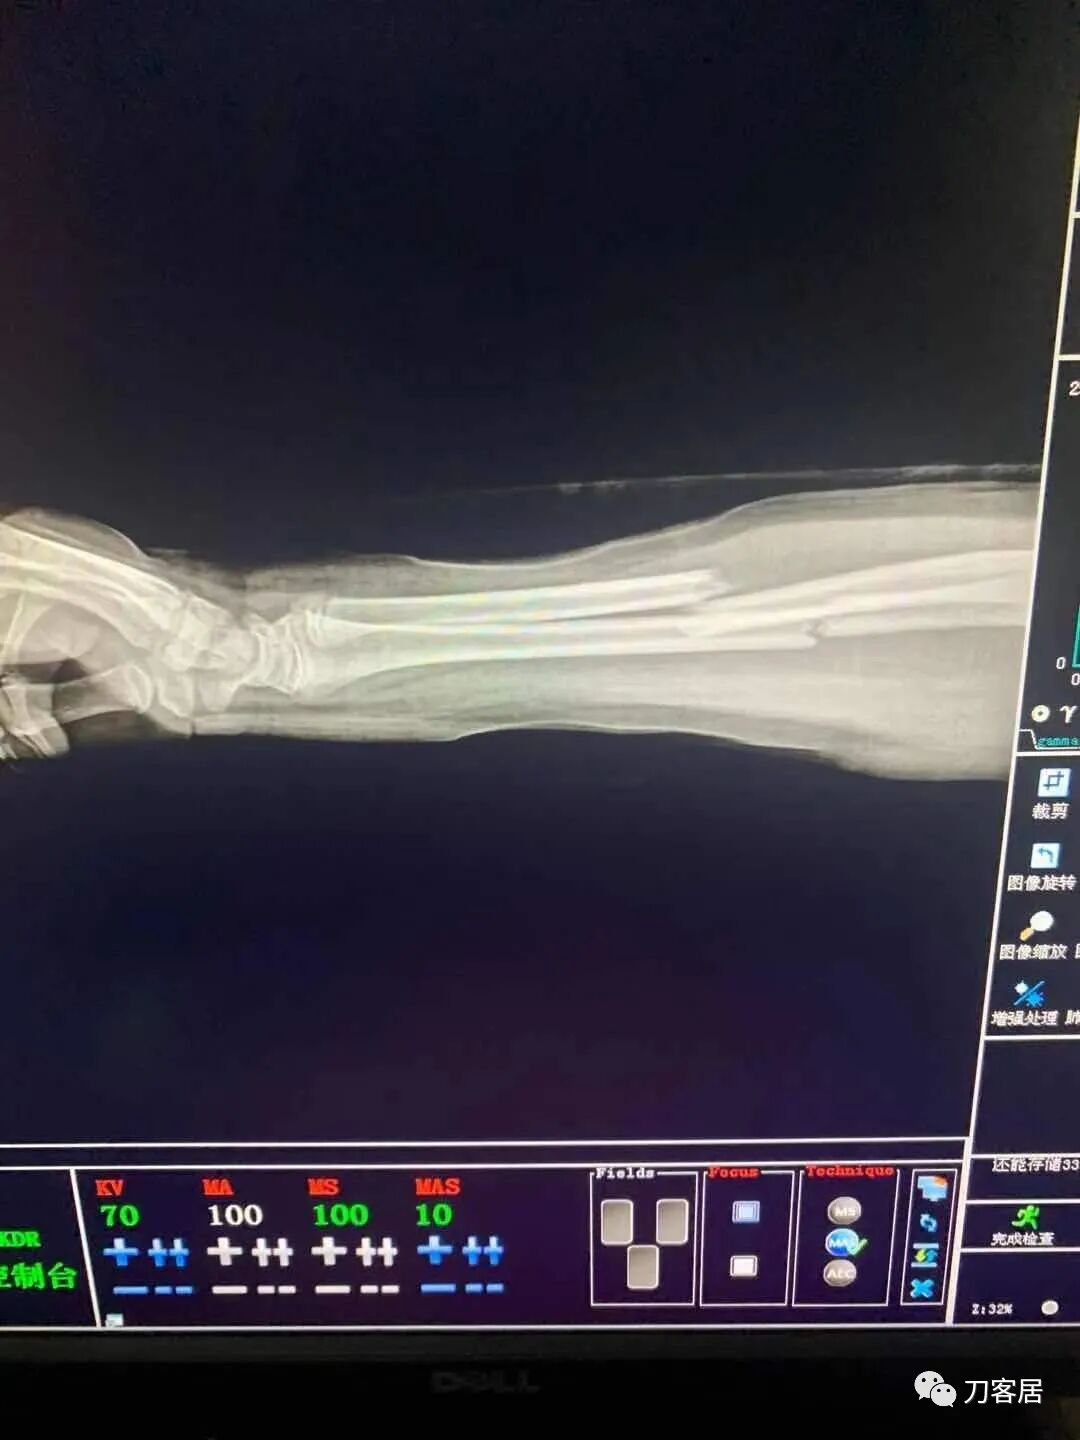

下面是这个6岁孩子,尺桡骨远端双骨折的术前及术后片子和外观照片。

1.  这是一个很简单的6岁儿童无移位的尺桡骨远端骨折。没有皮肤损伤,没有移位,没有骨折碎块儿。

2.  这个骨折处理起来也很简单,单纯的打石膏托或者中医的小夹板,或者正规的包括腕关节和肘关节的管型石膏外固定4周即可治愈该骨折。实在不行,如果这个孩子比较听话,不太调皮的话,用一本书,一个三角巾悬吊固定4周,都可以治愈该骨折。但是给这个患者用外固定架做了手术,而且桡骨远端的几颗克氏针距离骨折线太近,其中一枚克氏针进入到骨折间隙内。从这个术中图片来看,术者的外固定手术技术也有待于进一步的提高。毕竟术者应该还很年轻。从X线片来看,前臂及手的尺侧有不透光影,应该还使用了外固定石膏绷带托,而且我猜测应该是高分子的石膏绷带托,这个是纯属猜测,不一定是对的,不过如何解释前臂尺侧的不透光影呢?如果真是用了石膏绷带外固定的话,那为啥要做手术呢?外固定架术后就不该再用石膏绷带托辅助了。